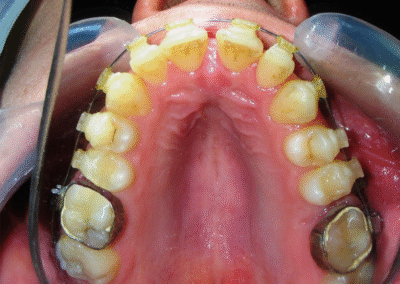

Intraoral Examination:

Absent #16, #36 and #46 , No Angle molar relationship . Projection of canines axes in class II relationship . Anterior open bite: Over Bite – 8 mm). Bilateral posterior crossbite: Involvement of upper posterior sectors with inverted buccal-lingual relationship. Moderate Crowding at the level of the upper and lower incisors. Acceptable Oral Hygiene with no periodontal issues

Was installed a Hyrax-type 10mm palatal expander of the Brazilian trademark Morelli® , modified by the author to be adapted to receive TADs microscrews, in order to initiate maxillary disjunction with MARPE (Mini-implant Assisted Rapid Palatal Expansion), TADS was installed with skeletal anchorage placed bilaterally having as references the roots of the maxillary canines and first premolars. Prior to insertion, local infiltrative anesthesia was administered using 2% lidocaine hydrochloride with 1:100,000 epinephrine. A total dose of approximately 0,8 mL per side (cortical infiltration technique). The TADs were inserted under aseptic conditions using a manual driver. Microscrew Evolution 1,6 Ø x 10 mm from the Argentine brand Odontit® . The Hyrax expander was then fitted and activated after 48 hrs .

Protocol of one activation per day was followed for a period of three weeks where the first clinical and radiographic evaluation was performed, showing clear signs of skeletal expansion, including the presence of a midline diastema. One more week of activations was added with a total of 28. The patient reported moderate headache during the first week of activation.